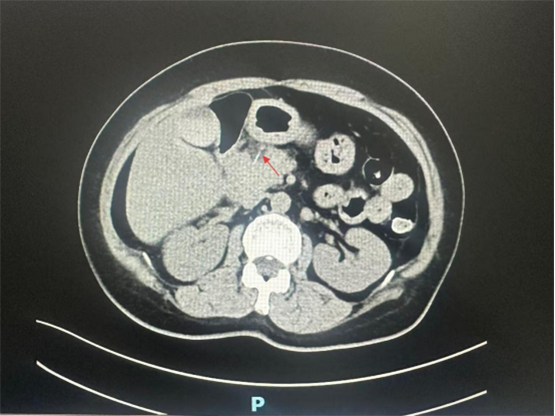

腹部CT显示胃窦水平与胰腺之间细条形高密度影,异物?胆汁淤积或泥沙样结石,遂转入肝胆外科继续治疗,继续胃肠减压,针对胃窦水平与胰腺之间异物,追踪病史10+天前误吞鱼刺,进一步行超声内镜,十二指肠及胃腔未发现异物,异物可能由胃腔穿入胰腺组织,也可能由十二指肠穿入胰腺组织,经全科讨论认为异物已经十二指肠壁进入胰腺,异物远端离肠系膜上静脉非常近,如不及时取出异物,有穿破肠系膜上静脉引起大出血风险。经消化内科会诊排除内镜取出的可能性,只有进行外科手术探查。在积极完善术前准备后进行手术治疗,为减少创伤,首选腹腔镜微创手术探查。

9月30日,肝胆胰外科喻智勇教授主刀为患者实施腹腔镜下手术探查术,术中见胰头下后方与十二指肠内侧环之间一炎症水肿区域,疑为异物所在位置,小心分离、解剖,结果发现异物为白色细长针状“鱼剌”,近端经十二指肠球降部穿出肠壁,远端经胰颈部进入胰腺,完整取出异物,仔细观察肠壁未见明显穿孔,胰腺实质无出血及胰漏。取出后发现异物为长约3-4公分鱼剌。术后患者恢复快,一周后痊愈出院。